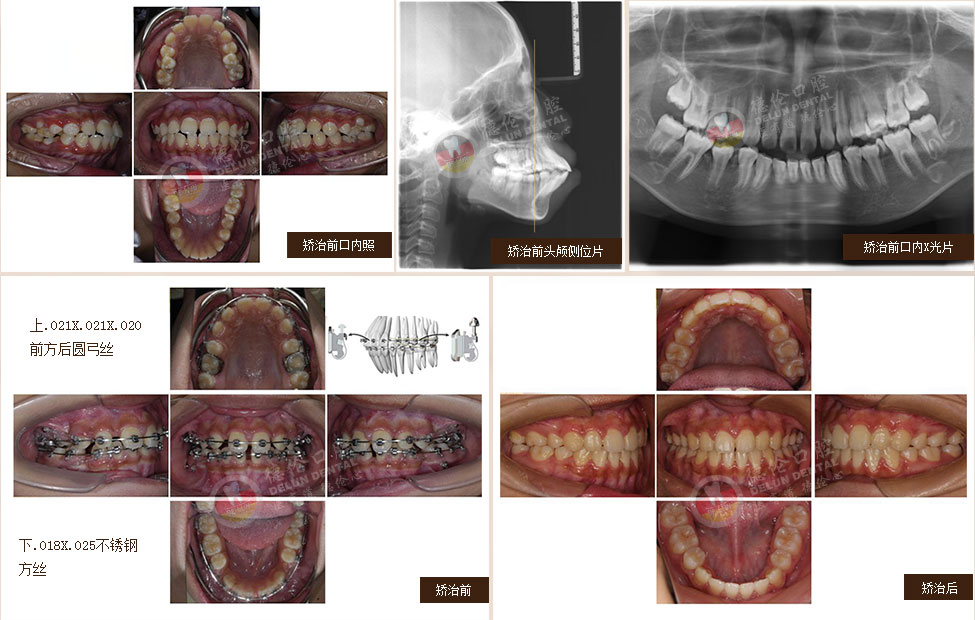

• 女:24歲

癥狀:牙列不齊、下頜第二、第三磨牙水平阻生,左側(cè)磨牙鎖牙合

矯治方法:拔除上頜及右下第一雙尖牙,左下第二雙尖牙以及2個下第三磨牙